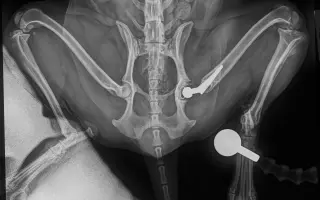

Sbírka je pro aktivního pejska Charlieho (Káju), který v říjnu 2025 podstoupil operaci cementované endoprotézy levé kyčle kvůli degenerativní coxartzróze. Samotná operace bez předoperačních a pooperačních kontrol vyšla na 64tis. Po dlouhé rekonvalescenci se opět vracel k normálnímu životu. Začalo se opět chodit na procházky, zatím ne žádné túry a vypadalo to, že vše bude v pořádku. Kontroly dopadli dobře, Charlie chodil i radostně pobíhal bez potíží. Už jsme si mysleli, že konečně bude mít klid od bolesti, ale bohužel začal náhle kulhat a chodit zadní částí těla do pravého boku. ❤️‍🩹

Nechali jsme tedy na veterině udělat orientační RTG snímky, bez přítomnosti ortopeda, byla již vidět luxace implantátu, proto jsme i během víkendu zkontaktovali MVDr. Jana Hnízda, který ho operoval a hned nás následující den pozval na RTG v sedaci. Bylo tedy zjištěno, že cement, který pojí umělou jamku s kostí se uvolnil a celý implantát jde tak v určitém pohybu do subluxace. 😥

Dorazili nám dnešní snímky, už ortopedicky přesnější